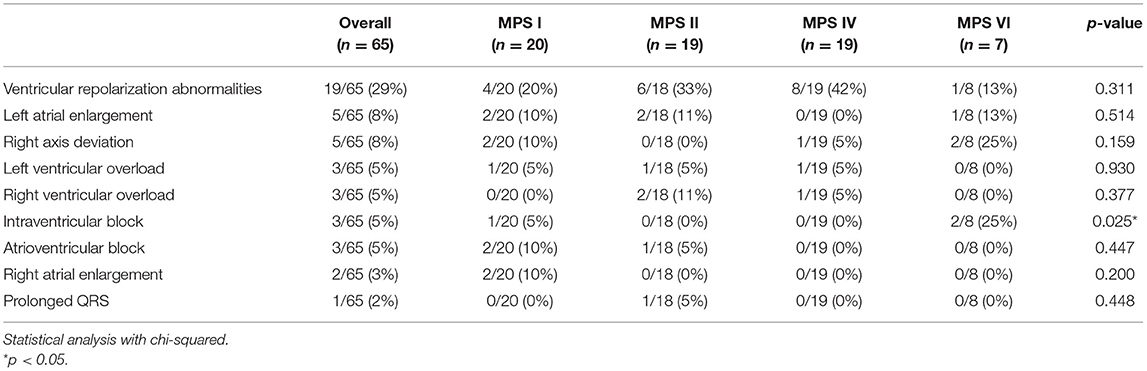

Electrocardiogram

Electrocardiograms were performed in 65 patients (45 children and 20 adults) at some point during follow-up. All patients had a sinus rhythm, although transient junctional rhythm was observed for one female with MPS IVA in the middle childhood. The most frequently observed finding was the presence of repolarization anomalies (29%) (Table 5; Figure 4A). Left ventricular hypertrophy (LVH) and left atrium enlargement were present in 5 and 8% of the patients, respectively. Atrioventricular block and long QT intervals were also occasionally observed (Figure 4C), as well as intraventricular blocks. As compared to children, adults had a higher prevalence of most of the ECG abnormalities (Table 6), particularly ventricular repolarization abnormalities (Figure 4A) and left atrial enlargement (Figure 4B).

Table 5. Prevalence of electrocardiographic abnormalities at the last available electrocardiogram, including both ERT treated and untreated subjects.